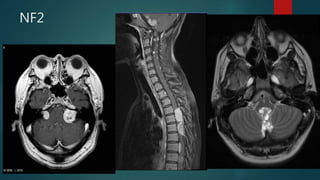

NF2

 MISME

• M: multiple

• I: inherited

• S: schwannomas

• M: meningiomas and

• E: ependymomas

 Rule of 2s

• neurofibromatosis type 2

• chromosome 22 (22q12) gene location

• bilateral vestibular schwannomas

• presents in 2nd-4th decades (around 20 years)

• initial prevalence estimated to be 1:200,000

• #31 Post contrast T1 axial imaging demonstrates bilateral enhancing masses in the cerebellopontine angle, larger on the left. Both can be seen extending into the internal acoustic meatii and are consistent with acoustic schwannomas. The fact that they are bilateral almost certainly indicates that the patient has NF2.  There are multiple enhancing nodular lesions spread throughout all the spinal canal and going through some vertebral foramina Mixed solid-cystic mass arising from the fourth ventricle and causing mass effect on the brainstem. There was also resultant obstructive hydrocephalus, not shown here. The mass appears to ‘ooze’ out of the foramen of Magendie. There was no associated spinal lesion. Classical ‘plastic’ ependymoma